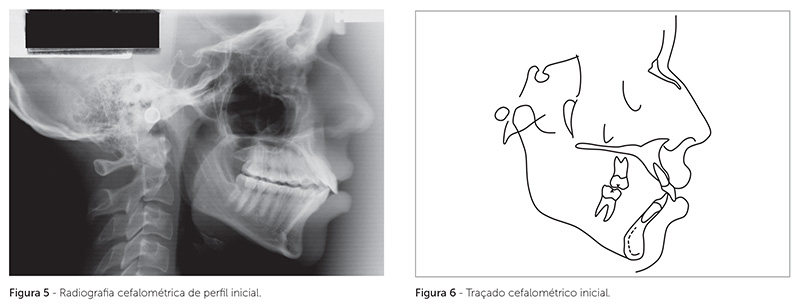

A paciente apresentava um padrão esquelético de Classe II, caracterizado por deficiência mandibular, com ângulo ANB de 6o (SNA = 82o e SNB = 76o) (Tab. 1). O perfil era convexo, com ângulo nasolabial obtuso, ápice nasal levemente desviado para a direita, face longa, com ausência de selamento labial passivo, terço inferior da face aumentado e linha queixo-pescoço curta (Fig. 1).

O exame intrabucal revelou a presença de má oclusão de Classe II, 1ª divisão de Angle, arcadas dentárias superior e inferior expandidas e assimétricas, sobressaliência de 6mm, mordida aberta posterior, com contato oclusal apenas nos segundos molares, e desgastes excessivos nas cúspides dos molares superiores e inferiores, devido a uma tentativa de ajuste oclusal (Fig. 1, 2). Os incisivos superiores e inferiores estavam protruídos e inclinados para vestibular, com arredondamento apical das raízes dos incisivos superiores (Fig. 3, 4, 5).